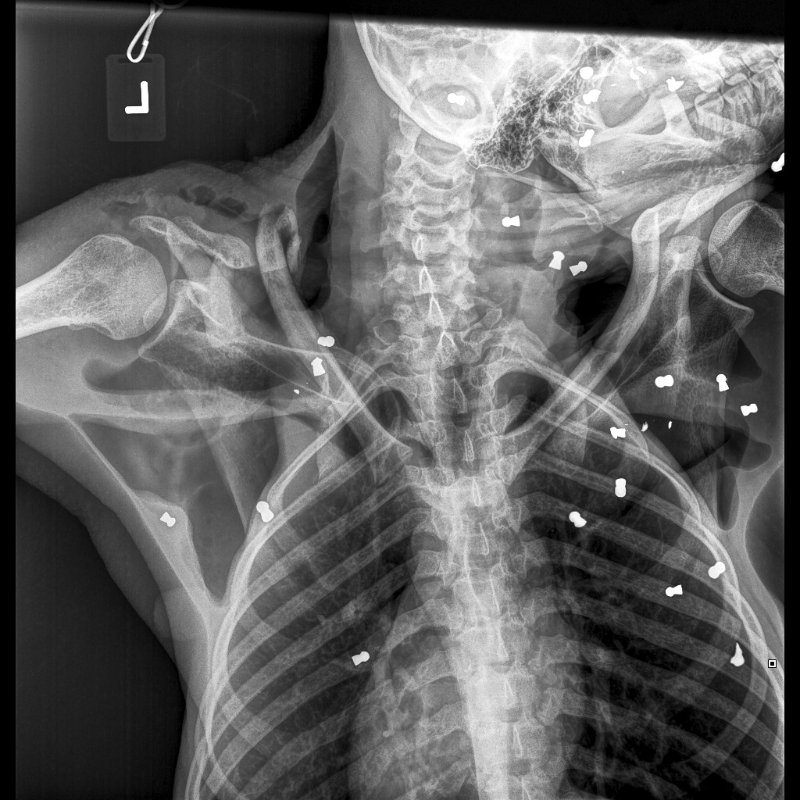

Orang-Utans, die aus solchen

Konfliktsituationen gerettet werden, kommen

oft mit gebrochenen Knochen, Schnittwunden und

Schusswunden in den Rettungszentren

an. Einige haben noch Dutzende von

Luftgewehrkugeln in ihren Körpern.